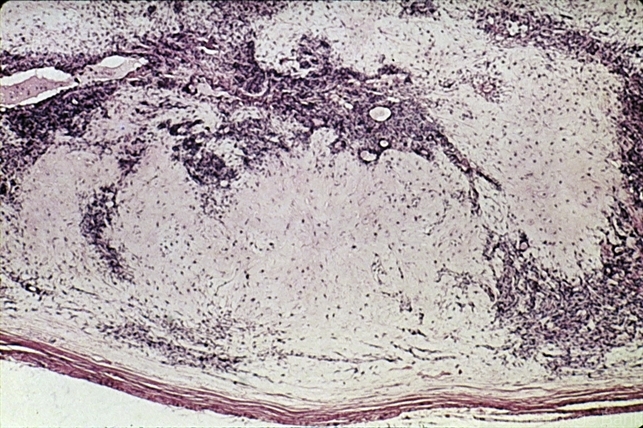

- Benign mixed tumor. Biphasic appearance is due to alternating, relatively acellular myxomatous spaces and cellular areas (H&E x40).